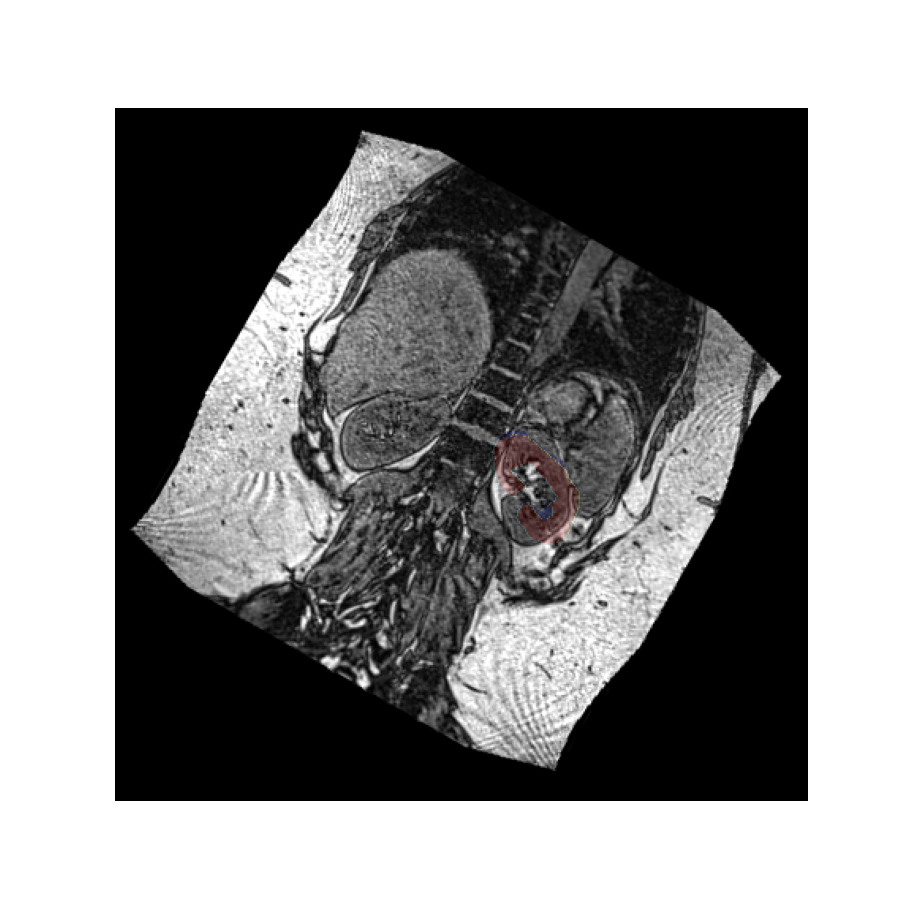

Let’s perform the above rotation again, but now passively using it only to reslice the values. We use the oppositive sign of the rotation vector to get a comparable result as before:

The rotated image looks exactly the same as in the previous example, but in this case the kidney mask is still in the same place. This is because the volume has not actually been rotated in space - it has merely been resliced at an angle so we see it in a different plane.